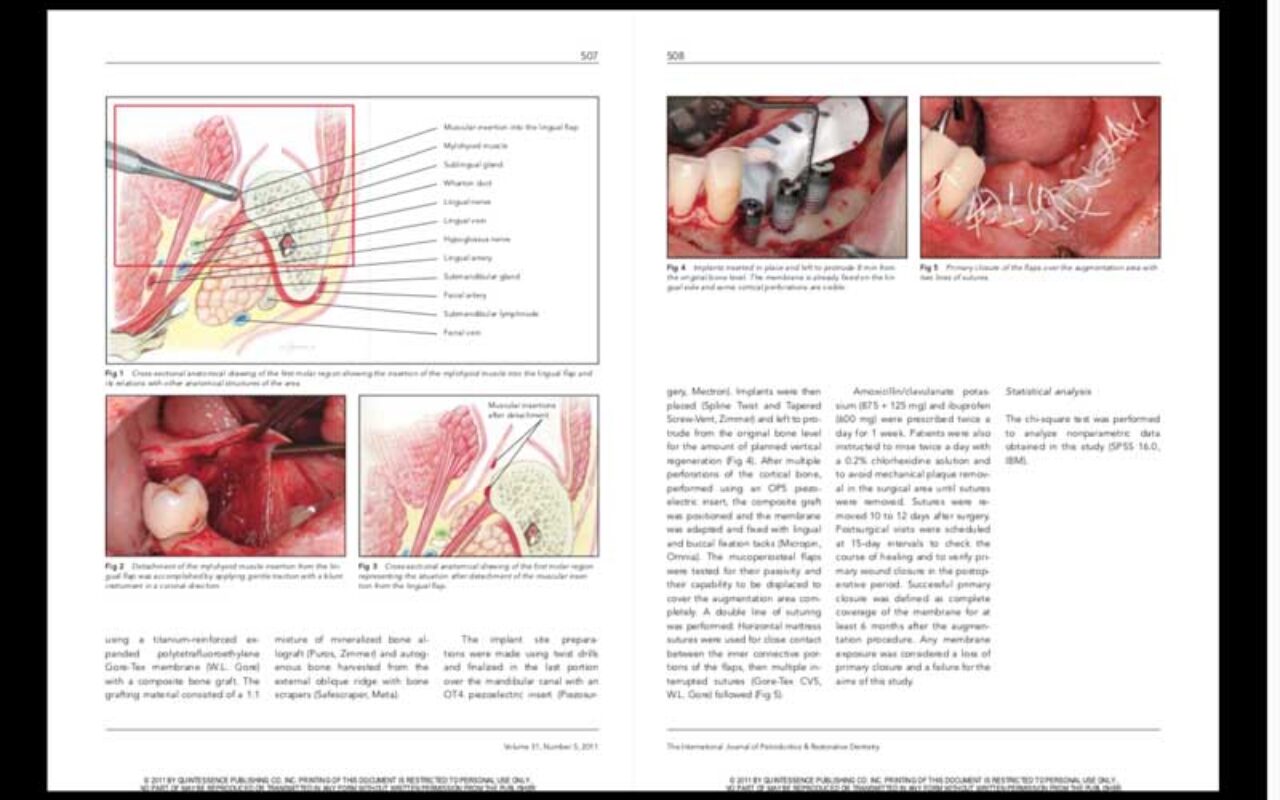

Dr. Marco Ronda

Dr. Marco Ronda

Management of a Coronally Advanced Lingual Flap in Regenerative Osseous Surgery: A Case Series Introducing a Novel Technique